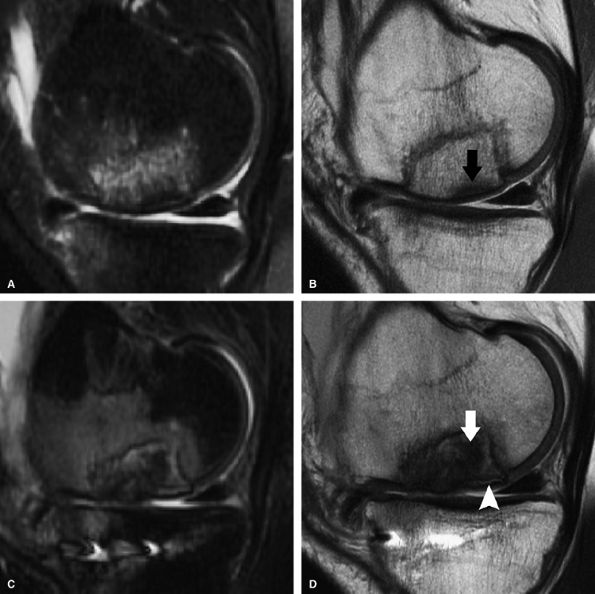

FIGURE 7.18 ● Prospective MR evaluation of a bone bruise in the knee of a 28-year-old man with a complete ACL tear. Sagittal fat-suppressed (A) and fast spin-echo (B) MR images obtained at the time of injury demonstrate characteristic bone marrow edema with compression of cartilage over the lateral femoral condyle (white arrow). A sagittal MR image obtained 19 months later (C) demonstrates proud subchondral bone with focal cartilage loss over the condyle (black arrow), as well as flap formation over the tibial plateau (arrowhead). (Reprinted by permission of SAGE Publications, Inc., from Am J Sports Med, in press.)

|